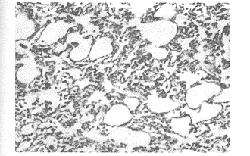

2.1.1 注射标准大肠杆菌菌株后,肺组织病理结果显示:给药后4小时光镜下可见肺泡腔狭窄,肺泡壁毛细血管扩张,肺泡腔内可见少数脱落上皮细胞及中性粒细胞渗出。随时间延长,肺泡腔狭窄逐渐增多,肺泡壁增厚明显。至给药后12小时,可见肺泡间隔增宽,粉染水肿状,肺泡腔内大量脱落上皮细胞和中性粒细胞浸润(见图1~3)。

图1 ALI组大鼠4小时肺组织病理(HE×200)

图2 ALI组大鼠8小时肺组织病理(HE×100)

图3 ALI组大鼠12小时肺组织病理(HE×100)